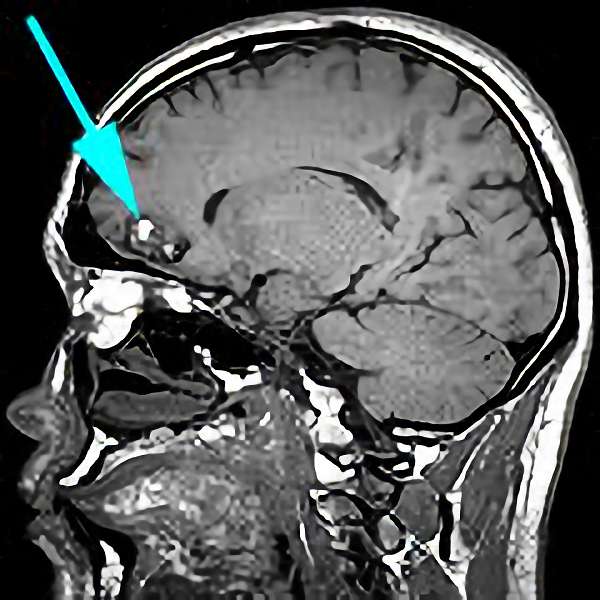

'19年7月

10代

富永

南田

脳室

海綿状血管腫

出血性

大阪府の病院

より紹介

No.No.30 手術前1

No.No.30 手術前2

No.No.30 手術後1

No.No.30 手術後2

CT/MRにより完全に摘出されたことが確認された